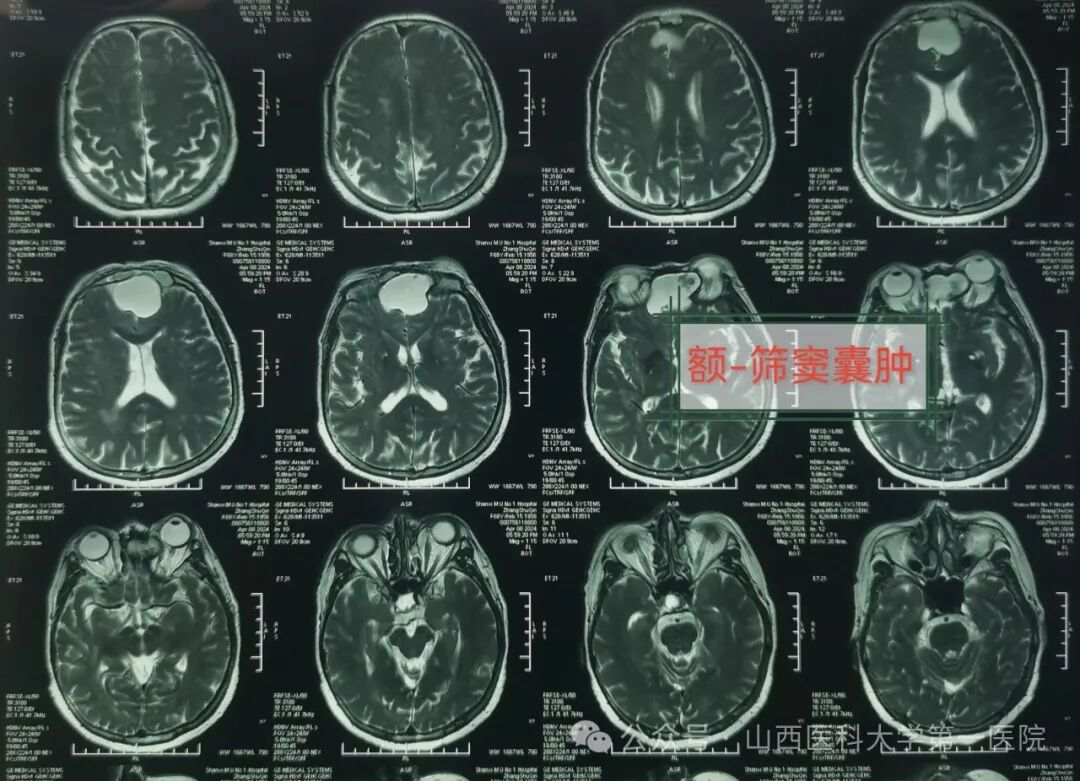

老年女性张某数月来出现头痛、前额部为主,最近发现视物模糊,视力呈进行性下降,且症状越来越加剧,又出现鼻涕中带血丝与嗅觉失灵,于是来到山西医科大学第一医院耳鼻咽喉-头颈外科就诊,经过医生检查后初步诊断为额-筛窦囊肿,侵犯眼眶、前颅底。

医生通过检查发现张某一侧眼球明显向前上方突出,眼球活动受限,单侧视力处于下降状态,鼻窦冠状位CT与MRI提示:额窦、筛窦充满混杂密度阴影,眼眶颅底受压,考虑鼻窦占位性病变引起。耳鼻咽喉-头颈外科主任皇甫辉主刀,术前制定了周密的手术方案,在全麻下行鼻内镜鼻窦囊肿涉眶与颅底根治切除术,术中显露术野,暴露病变组织,发现病变位居单侧筛窦与额窦,已侵犯单侧眼眶及球后与前颅底,病变范围广,内镜下切除鼻腔筛窦与额窦病变组织,开放额窦,切除部分前颅底病变组织,并以人工脑膜修复缺损,最终完整切除病变,手术获得圆满成功。